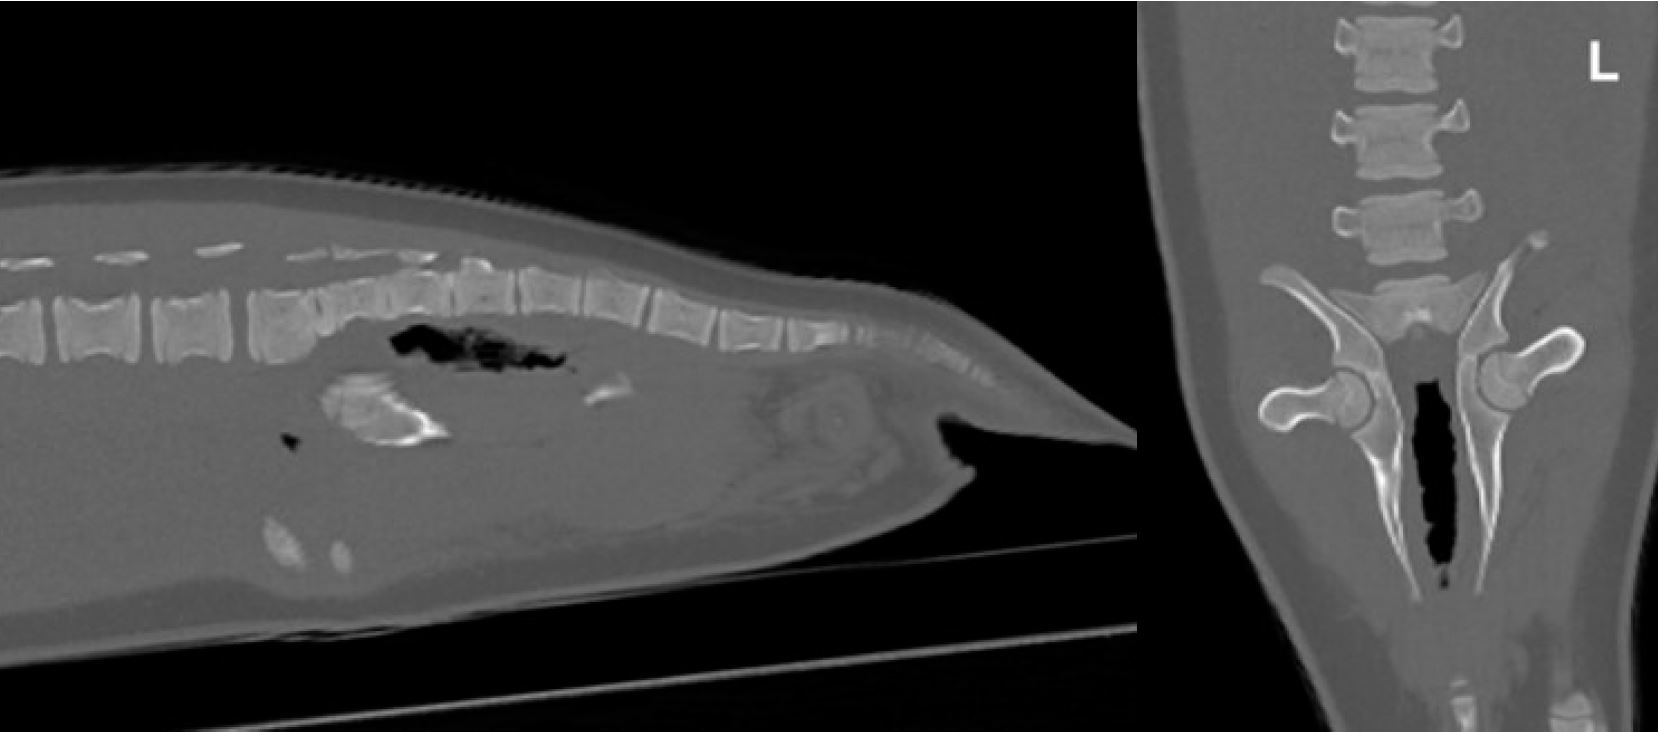

Елвіс продемонстрував ненормальну ходу та, ймовірно, біль у тазі. При таких проблемах, як переломи хребта. Для виключення вивиху або перелому кісток таза виконано КТ (мал. 3). КТ не виявила ознак переломів і вивихів.

Малюнок 3: Не було виявлено аномалій у будь-якому напрямку у кістковій реконструкції.